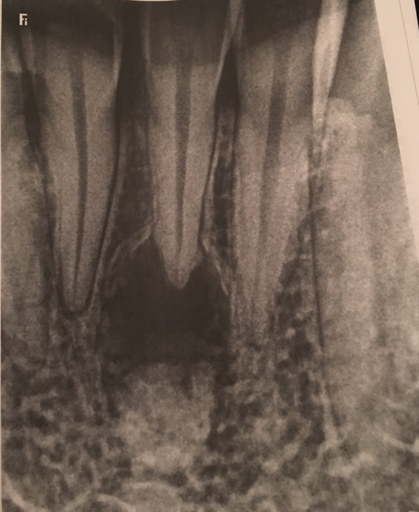

It is not abnormal for a tooth to take some time to fully erupt, especially if the primary tooth was removed prematurely. Having your dentist take an anterior radiograph at your sons next routine hygiene appointment will allow the dentist to see if there is anything blocking the eruption of the tooth. Without any dental radiographs of the anterior (front) teeth, it is hard to predict the eruption pattern. Usually it is nothing to worry about, however, an orthodontist can help the tooth fully erupt if necessary.